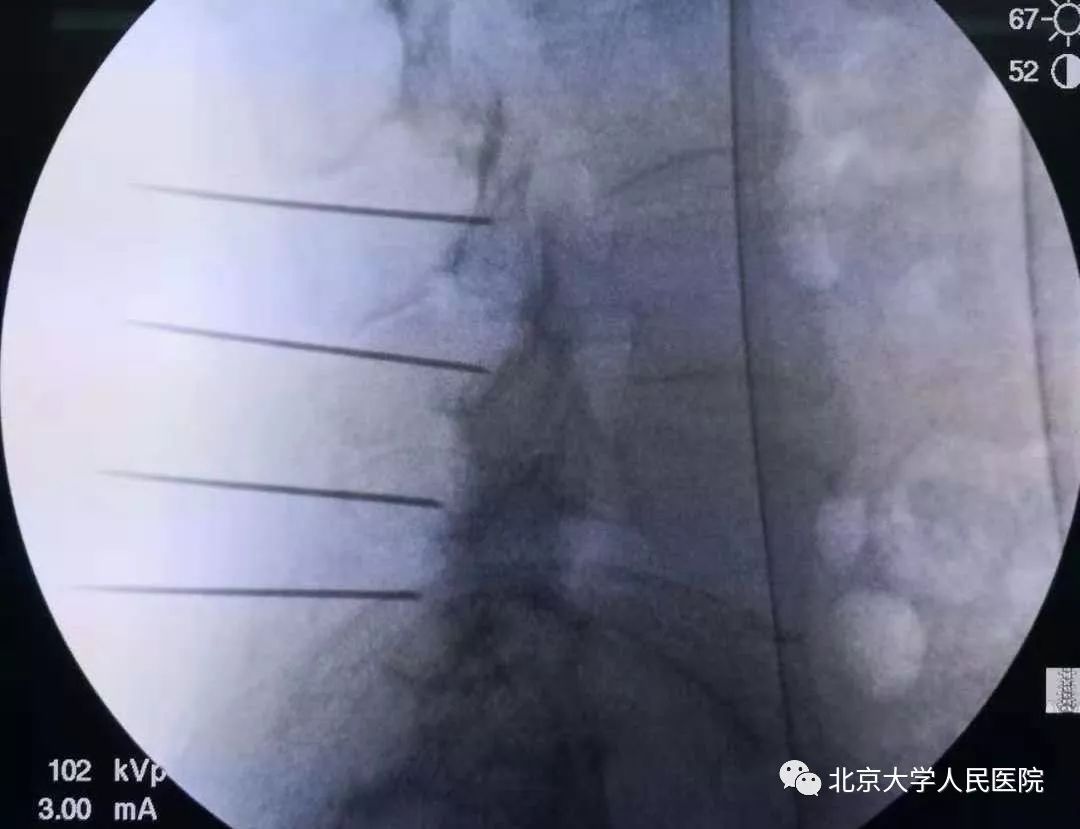

内脏神经丛毁损治疗顽固性内脏痛

将无水酒精注射至内脏神经周围,使神经发生变性,这样可以阻断内脏疼痛信号的传导。内脏神经毁损常用来治疗各种顽固性内脏痛,尤其是腹腔和盆腔肿瘤导致的疼痛,例如:胰腺癌、胃癌、肝癌、胆囊癌导致的腹痛。